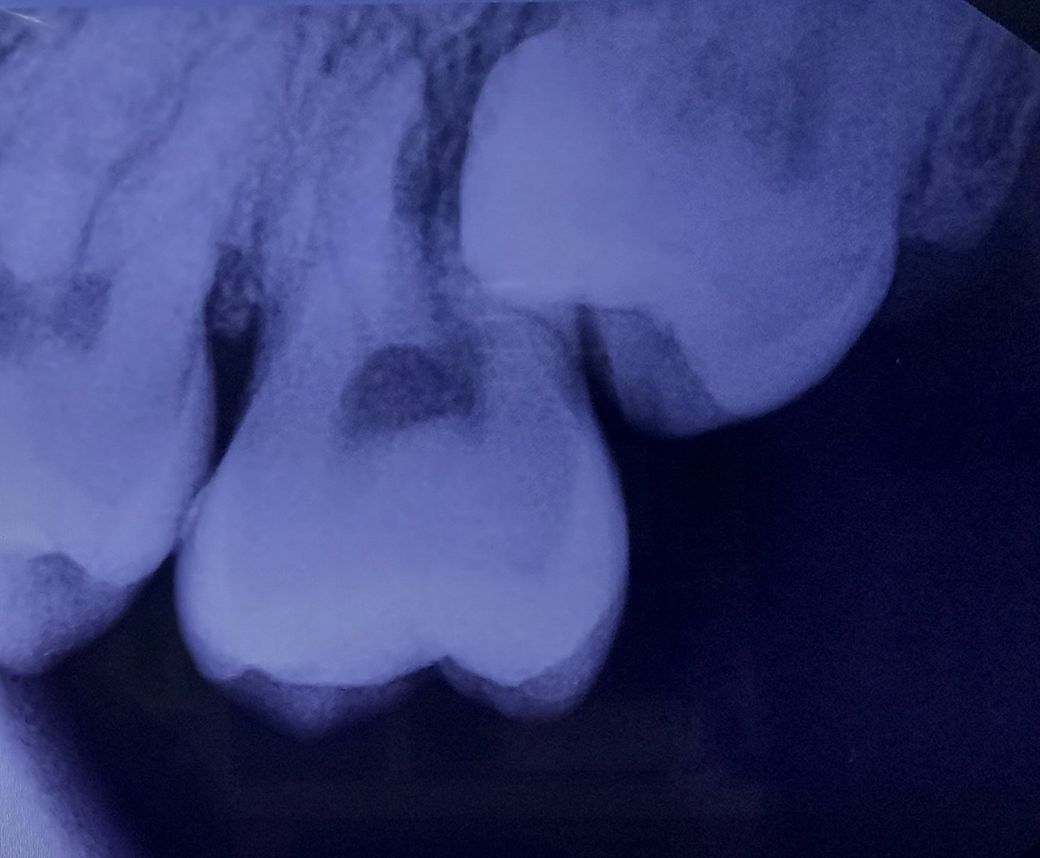

사랑니 때문에 어금니를 뽑아야 하는 상황인가요?

어금니 밑면에 충치 때문에 치과에 갔는데 사랑니와 어금니를 같이 발치하고 임플란트를 해야한다고 들었습니다.

어금니를 뽑아야 하는 상황인가요? 가능하면 신경치료 정도로 하고 제 치아를 남기고 싶습니다

• 2번 째 사진

올려주신 사진은 평면으로 나와있어 사랑니가 앞에 치아뿌리가 녹고있는건지 정확한 판단이 힘듭니다.

사랑니로 인해 뿌리가 흡수되면 발치가 고려되나 그렇지 않다면 발치가 필요없게 됩니다.

자세한 사항은 ct를 찍어 뿌리와 사랑니사이의 관계를 보는것이기 때문에 추가 검사를 추천드립니다.

올려주신 사진만 봤을때는 사랑니과 앞의 치아를 같이 빼야할 가능성이 높습니다.

더 정확한것은 씨티를 봐야 알 수 있습니다.